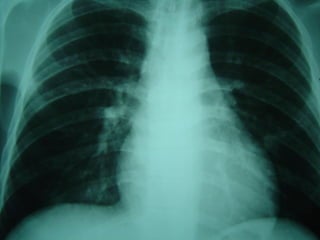

MICOSES PULMONARES

 RADIOLOGIA – ASPERGILOMARADIOLOGIA – ASPERGILOMA